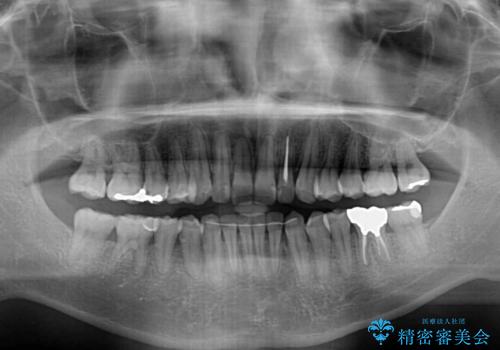

前歯のデコボコと下顎の八重歯 インビザラインによる矯正治療

- 前歯のデコボコや八重歯を気にして来院された患者様です。

インビザラインを用いて、歯列を整えることとしました。

下顎前歯は後戻りを起こしやすいため、舌側を細いワイヤーで固定し、マウスピース型リテーナーで保定を行うこととしました。